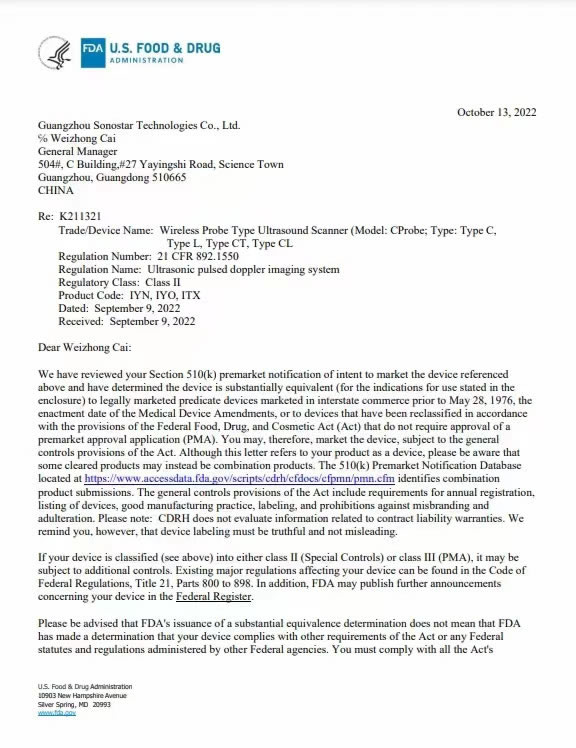

Sonostar successfully participated in the RSNA exhibition

SonoStar successfully participated in the RSNA Medical Exhibition in the United States, attracting mVIEW MORE →2025-12-05 -